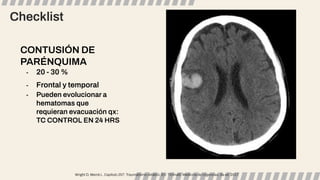

CONTUSIÓN DE

PARÉNQUIMA

- 20 - 30 %

- Frontal y temporal

- Pueden evolucionar a

hematomas que

requieran evacuación qx:

TC CONTROL EN 24 HRS